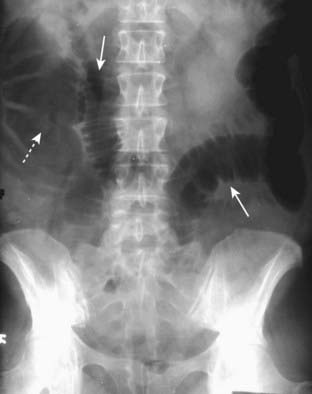

image

Figure 14-13 Mechanical large bowel obstruction.

The entire colon is dilated (dotted white arrows) to a cut-off point in the distal descending colon (solid white arrow), the site of this patient’s obstructing carcinoma of the colon. Some gas has passed backwards through an incompetent ileocecal valve and outlines a dilated ileum (solid black arrow). Notice that the large bowel is disproportionately dilated compared to the small bowel, a finding of large bowel obstruction.